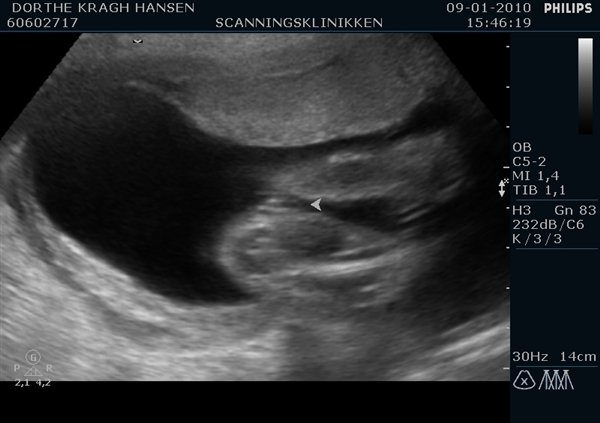

Første billede siger sig selv og andet er...ja hendes lille tissetrold